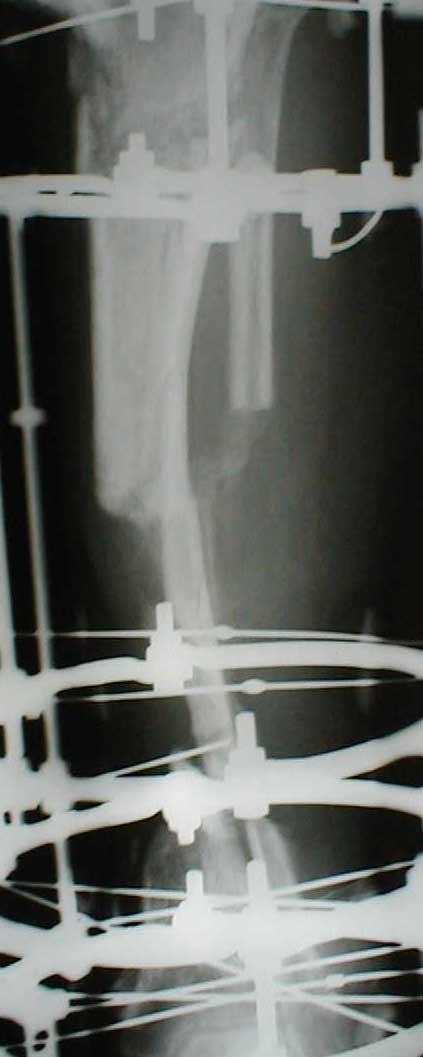

Dorogie kollegy,Have a nice day,Ja bi hotil obsuzdat' s Vami dvuh bolnih, kotorie postupili segodnjia ko mene. Pervy iz nih (OI) bolnoi s otkritoi tiazeloi mehanicheskoi travmoi Rt. leg segment v rezultate DTP, ot chego on imeet sledueshie povrezdenjia:- Otkrity perelom kostei pravoi goleny v srednei i niznoi ee trety s poteriem okolo 10 cm. kostnogo veshestva ot bolshebersovoi kosty, - Povrezdenjia a.tibialis post. s massivnim povrezdeniem zadneoi gruppy musculs goleny,- Malobersovjia kost' imeet segmentarny perelom, ee nizny fragment (kak Vi videte na foto) vistupaet na kozy okolo VNUTRENNOI Lodizky! - Traumaticheski Shock 2-3Drugih povrezdenjia net.

Nemedlenno bolnoi bil' intubirovan i provedeny vse protivoshokovie procedury, pravjia golen' bila pomeshenjia na apparat' Storm, dla reduksii kostei posle ee fiksasii k apparatu s pomoshio 2 spitsy 3mm D. Provedena Repozitsia pereloma i fiksirovana STORMOM vremenno, za tem sosudisty hirurg vypolnil 2 obhodnih anastomosa for a. Tibilis posterior, bili udaleny bolshie chasty iz musculov zadnoi gruppy goleny v predelah "vozmozno vedemih" zdorovoi tkany, oblast' pereloma promita by N. sol. 0.9% - 12 L. Zatem byla proizvedena okonchatenjia reduksia pereloma posle umerennoi traksii goleny na apparate, i fiksasiya pereloma s pomoshio apparata vneshnei fiksasii. Tak, Kakie soobrazanjia po dalneshemu vvdenjia bolnogo? On poluchaet antibiotiky i bolshie dozy LMH (Clexane 80 X 2) i vse ostalnoe......

Zdes' snimky posle poslednego montazha apparata prilagaiutsa

Yours Castro

Кликните для загрузки файла IMG_0501.jpg

13KB (14124 bytes)

Может быть не совсем в тему, но... Скажите, а чем вызвана такая необычная компоновка аппарата: кольцевидный фиксатор и стержни? На первый взгляд так теряются преимущества монолатеральной стержневой фиксации (легкость перевязок) без достаточной компенсации достоинствами классического ВКДО Илизарова?

"Необычная" фиксация, предполагает осуществление максимальной стабильности проксимального фрагмента б\б кости. Как ее добиться - дело лечащего врача. При всем уважении к монолатеральным фиксаторам, лучше пожертвовать неудобствами при перевязках, чем нестабильностью фрагментов. Если поставлена цель сохранения конечности, то на данном этапе стабильность это - пункт № 1.

Ito vizvanno tem, chto, ja hotil dobitsa bistreshei stabilnoi fiksasii, chto bi dat' sosudestomu hirirgu vozmoznost' rabotat' po medialno-zadnoi poverhonoste, u menjia nibilo dostatochnoe vremjia, dla togo, chto bi provodit' spisy, ih natiagivat' i t.d. i t.p. pre itom ja ni narushal prinsepov vneshnei fikasii dla fixasii poddobnih perelomov. U manjia bili pod rukoi fixatory Hoffmana, i drugie unilateral fixatores, no ja ni stal imi polzovatsa, potomuchto, na moi vzglad', oni malo effectivnie dla dannogo vida povrezdenjia, t.k., oni sozdaiot bol'shoi richag, v rezultate- ita vliaet na stabil'nost', ossobenno v distalnih otdelah, ito kak pravilo, prevodit' k zametnomu oteku nize pereloma, a tut mi smogli provodit'sterzny v teh ploskostiah, kororie nam udobnie v udobnih mestah sobludjia prinsepov "bistro, stabilno, minimalno"

Malo togo, Unilateral frames, ni sposobnie k dalnishemu razvetio, i rano ili pozdno predetsa perehodit' na Ring fixators, tak, chto luche iz nih i nachinat', a voprochem, u kazdego vracha est' vsai vzglady i biomechanicheskie soobrazenjia na opredelennio temu, u opredellnogo bolnogo, i ni vazno kakogo sveta koshky, i vazno chto ona lovit' mish'.